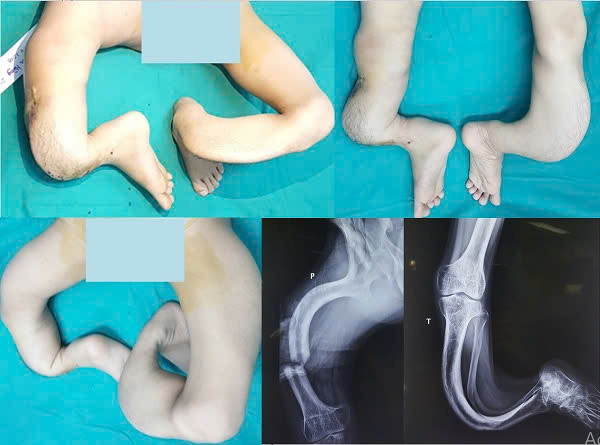

Hoặc như ca bệnh “Hoàng tử ếch” cũng là một trường hợp rất đặc biệt. Do cả 2 chân của bệnh nhân bị biến dạng cong queo như rễ cây suốt 27 năm ròng rã từ khi mới sinh ra nên bệnh nhân chỉ có thể đi lại bằng đôi tay của mình giống như dáng đi của một con ếch. Sau khi được chữa trị, bệnh nhân giờ đây đã trở thành một thanh niên có dáng đi hoàn toàn giống như bình thường. Anh đã tự mở một xưởng sửa chữa điện tử lớn, mở các lớp đào tạo về nghề sửa chữa điện lạnh cho rất nhiều các bạn trẻ khác. Đó là những ca phẫu thuật thay đổi cả số phận và cuộc đời của người bệnh.

| Đôi chân của bệnh nhân trước khi được phẫu thuật. |

| Đến nay, chân của bệnh nhân đã được chỉnh thẳng như người bình thường. Trong y học, kết quả này thực sự là một kỳ tích. |